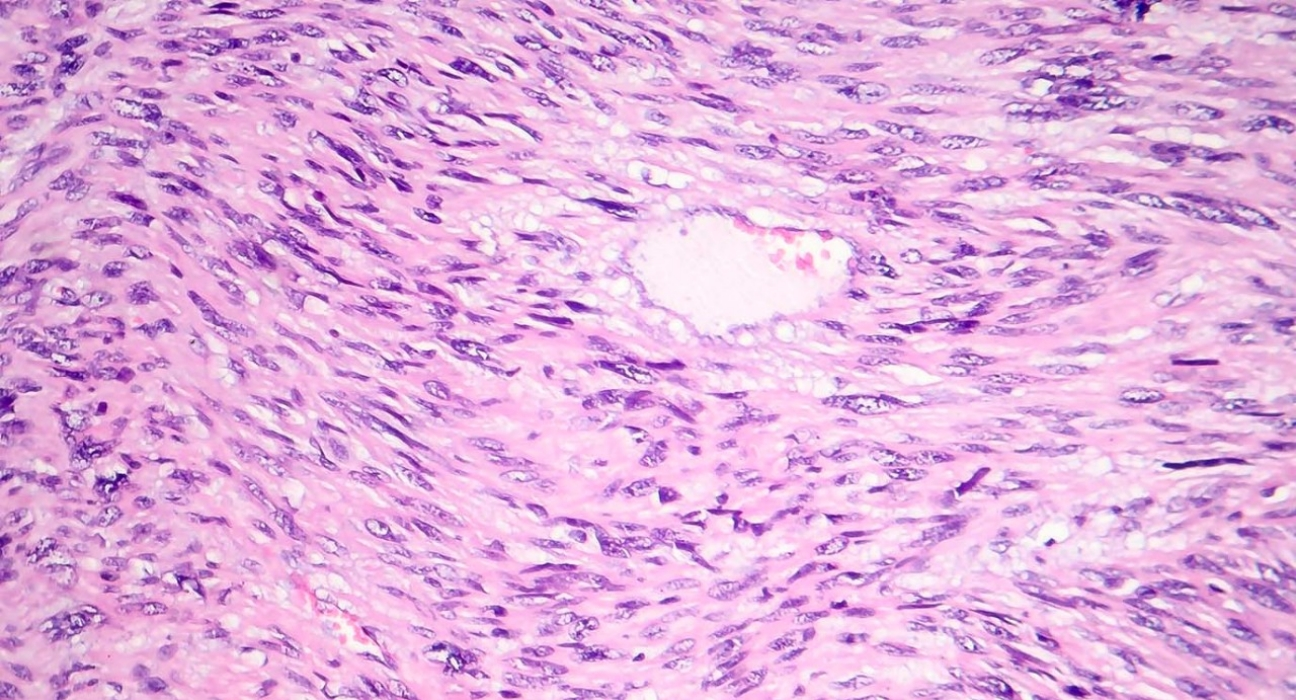

图片来源:MD安德森